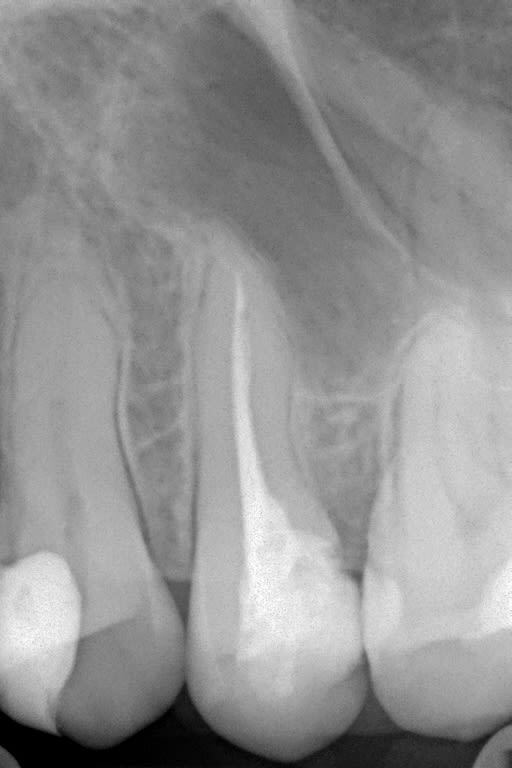

les radios

1 vdjkow - Eugenol

2 yf6iyx - Eugenol

A la vue des radios, je change d'avis. Es tu sûr qu'il y a des kystes? Demande une pano puis cone bean. Et tu vires l'endo esclusif, de toute façon.

au vue des radios je ne vois pas de faute, l'endo est pas parfaite mais loin d’être dégueu non plus

a la vue des radios ,ils sont ou les kystes ? et elles sont ou les couronnes ?

Exact, on ne voit pas de couronnes. Moi, je ne vois pas non plus de Kystes.

ce sont les radios de 2013, je n'ai pas de clichés de ce jour c'est mon correspondant qui a vu le patient